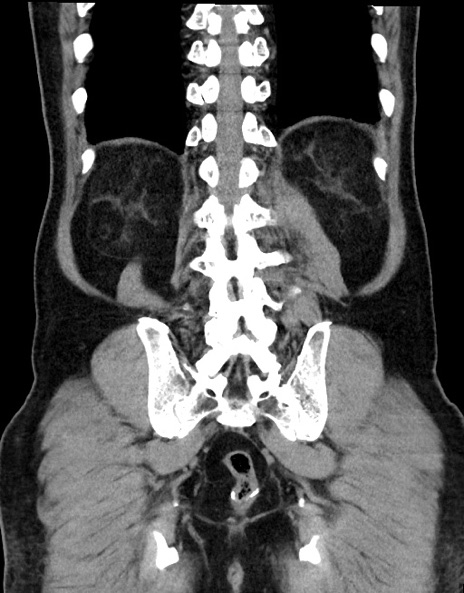

症例15(冠状断像)

【症例】70歳代男性

【主訴】腹痛

【現病歴】今朝から腹痛あり。全体的に痛い。特に左上の方。排ガスが今日はない。冷や汗が出る。

【既往歴】直腸癌術後

【身体所見】左側腹部〜上腹部に圧痛あり。腹膜刺激症状明らかなではない。軽度反跳痛。左下腹部に術後瘢痕あり。

【データ】WBC 7700、CRP 0.02